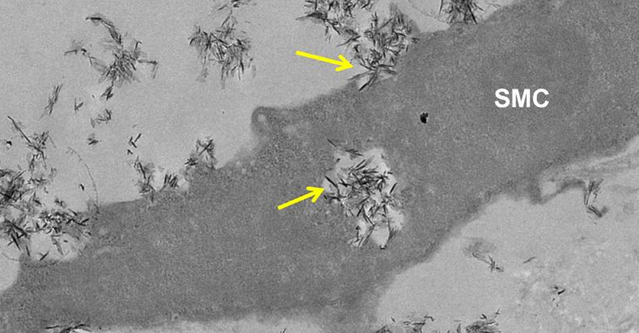

鈣化是心臟發作和中風的主要危險因素。磷酸鈣(CAP )的晶體可導致血管硬化,它們通常發現于骨骼和牙齒中,隨著年齡增長在軟組織中建立或作為疾病的一個結果。這可能會導致動脈粥樣硬化患者的并發癥,這是英國的一個死亡主要原因,它會導致動脈變厚,并且有被阻塞的危險。

在由英國心臟基金會資助的研究中,研究人員發現,微小的CAP晶體被血管細胞所吸收,從而導致異常高濃度的鈣離子,這已被證明是有毒的。他們發現,血液中的兩種蛋白質,胎球蛋白-A和白蛋白,可減緩血管細胞對CAP晶體的吸收,從而降低鈣離子的釋放和防止損傷。